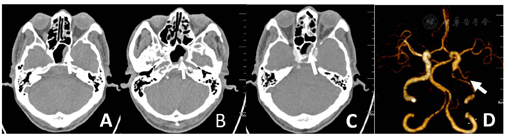

腰穿及影像学检查:腰穿见有清亮脑脊液流出,测压150 mm H2O;脑脊液体液细胞学:淋巴细胞93%、激活性淋巴细胞3%、激活性单核细胞2%、红细胞偶见,考虑存在穿刺伤;脑脊液分析(流式法):潘氏反应试验阳性(2+)、白细胞203×106/L(参考范围:0~8×106/L)、单个核细胞数198×106/L、单个核百分比97.6%;脑脊液生化:脑脊液总蛋白113.4 mg/dl(参考范围:0~50.0 mg/dl)、脑脊液糖94.7 mg/dl(参考范围:45.0~79.2 mg/dl)(指尖血糖14.0 mmol/L);血液、脑脊液细菌培养、宏基因测序阴性。双侧锁骨下动脉彩超:右侧锁骨下动脉斑块形成(狭窄率<50%),左侧未见明显异常;颈动脉彩超:双侧颈动脉球部斑块形成(狭窄率<50%),双侧颈总、颈内、颈外动脉、椎动脉未见明显异常;下肢深静脉彩超未见明显异常。胸部CT:右肺及左肺上叶尖后段散在微小结节。2019-08-08颅脑CT血管造影(CTA):左侧颈内动脉颈段末段及岩段节段性狭窄,相应管腔中-重度狭窄,远端分支较对侧稍显稀疏;双侧颈内动脉虹吸部多发钙化斑块,未见狭窄;右侧椎动脉颅内段钙化斑块,轻度狭窄;左侧大脑后动脉P1段局限性狭窄(图2)。颅脑MRI增强:左侧额顶枕叶脑沟内多发异常信号,左侧海绵窦较对侧增宽,左侧颈内动脉周围环形低信号(图3),建议进一步检查。2019-08-20颅内动脉斑块高分辨磁共振成像(HR MRI):考虑蝶窦炎致左侧海绵窦血栓性静脉炎,伴左侧颈内动脉(left internal carotid artery,LICA)大部腔内血栓形成,左侧大脑半球多发亚急性梗死;RV4近段易损斑块,管腔轻度狭窄(图4,图5,图6)。

注:A~C颅脑CT箭头所示为左侧蝶窦黏膜增厚,D颅脑CTA箭头所示为LICA狭窄、LMCA远端分支稀疏;CTA=CT血管造影,LICA=左侧颈内动脉,LMCA=左侧大脑中动脉

注:A、B颅脑ADC箭头所示为低信号影,C颅脑MRA为LICA颅内段未见显影;ADC=表观弥散系数,MRA=磁共振血管造影

注:A~D箭头所示为T1黑血序列蝶窦窦腔黏膜明显增厚,LICA管腔增宽、管径增粗;E~H箭头所示为T1强化黑血序列蝶窦窦腔黏膜明显强化、以左侧壁为著,LICA腔内为T1WI稍低高混杂信号影充填;HR MRI=高分辨磁共振成像

头痛是本例患者最初的临床症状,导致CST的误诊较为常见,因此影像学检查对于该罕见疾病的确诊至关重要。SCHUKNECHT等[12]研究表明,切片厚度为3 mm以下的颅脑CT可以显著提高诊断CST的能力。CST直接体征包括海绵窦扩张或填充缺损,有几项研究发现侧壁隆起也是CST最常见和最敏感的影像表现[13]。CST的间接影像学包括颈内动脉海绵窦段变窄或闭塞、海绵窦壁相邻硬脑膜强化增强、眼球突出或继发性血栓形成—特别是上眼静脉、岩静脉或乙状窦[14,15]。本例患者在颅脑MRI增强可见左侧海绵窦区增宽、扩张(图3),颅脑CTA提示颈内动脉狭窄,经过HR MRI证实为血栓(图6)。有文献报道全脑血管造影也为诊断CST的有效方法,然而只有42%的患者能够看到海绵窦,因此全脑血管造影不被作为常规检查或早期检查[16,17]。

本例患者临床症状最初只有头痛,后逐渐出现上睑下垂及眼肌麻痹,但全程无明显的眼球突出、结膜水肿,是导致患者延误诊断的主要因素。CST相关的血栓性静脉炎还可能会扩散到颈内静脉,出现Lemierre综合征[21]。同时感染可以通过颈静脉扩散到肺血管系统,导致肺脓肿、肺炎或脓胸[22]。CST最危险的并发症是海绵窦感染通过无瓣膜硬脑膜窦或脑静脉和导静脉传播,出现硬膜下脓肿、脑脓肿和颅内静脉窦血栓形成等颅内病变[23]。CST的脑膜旁炎症或明显的细菌从海绵窦迁移到脑脊液中可能分别导致脑炎或脑膜炎。此外,感染可引起血管炎,导致走行于海绵窦的颈内动脉痉挛[24]、血栓形成致狭窄或闭塞[18]。多达30%的CST幸存患者会出现长期后遗症,包括动眼神经麻痹、失明和垂体功能不全[25]。如本例患者颅脑MRI增强可见左侧额顶枕叶脑沟内多发异常信号,结合患者DWI考虑脑梗死引起的血-脑脊液屏障破坏后出现强化,不考虑颅内转移病变(图3)。本例患者颅脑CTA证实其存在明显LICA重度狭窄(图2D),本例患者梗死部位均在颈内动脉供血区(图4,图5),12 d后行颅脑HR MRI证实颈内动脉闭塞,考虑为血栓形成导致(图6)。海绵窦段颈动脉壁炎症目前被认为是缺血性并发症的来源,本例患者合并多发脑梗死,虽然存在脑血管病危险因素糖尿病,颈内动脉超声提示颈内动脉斑块形成,辅助检查颅脑CTA可见明显颈内动脉重度狭窄,但患者脑梗死面积非颈内动脉闭塞大面积梗死,而是多发散在梗死;颅脑HR MRI可见颈内动脉充填物为长条形的血栓信号影,未见动脉粥样硬化斑块信号影,与海绵窦段颈动脉壁炎症致颈内动脉血栓形成有关,因此考虑本例患者脑梗死机制可能为血栓栓塞机制。